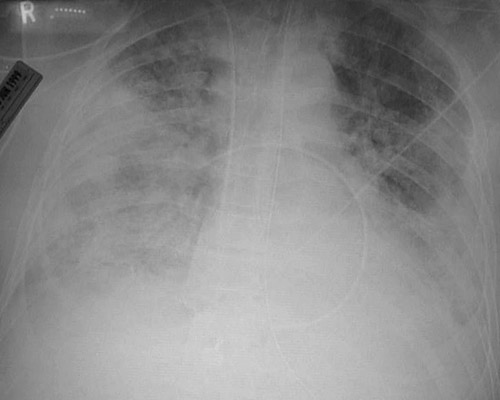

![]() | The portable AP chest radiograph above reveals diffuse small opacifications in all lung fields in a patient who was developing diffuse alveolar damage (DAD) over the past few days. The radiograph below demonstrates the worsening opacifications that are nearly confluent three weeks later at a more advanced stage of DAD. |